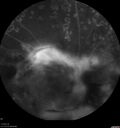

Pregnant - 25 weeks - new onset PDR and DME both eyes - Treated with PRP and ozurdex294 views29 year old female. Patient is 25 weeks pregnant and having flare up of retinopathy in both eyes. She states it is worse in the left. Patient has trouble with distant vision. At most recent visit, 1 years ago, VA was 20/20 OU. Two years ago anterior uveitis x 1 episode with normal labs (HLAB27, FTA, ACE, Lyme). 2017-2020 – Lucentis for DME left eye only.

PMHx: Type I DM since teenager, hyperlipidemia

BP was normalOct 19, 2021